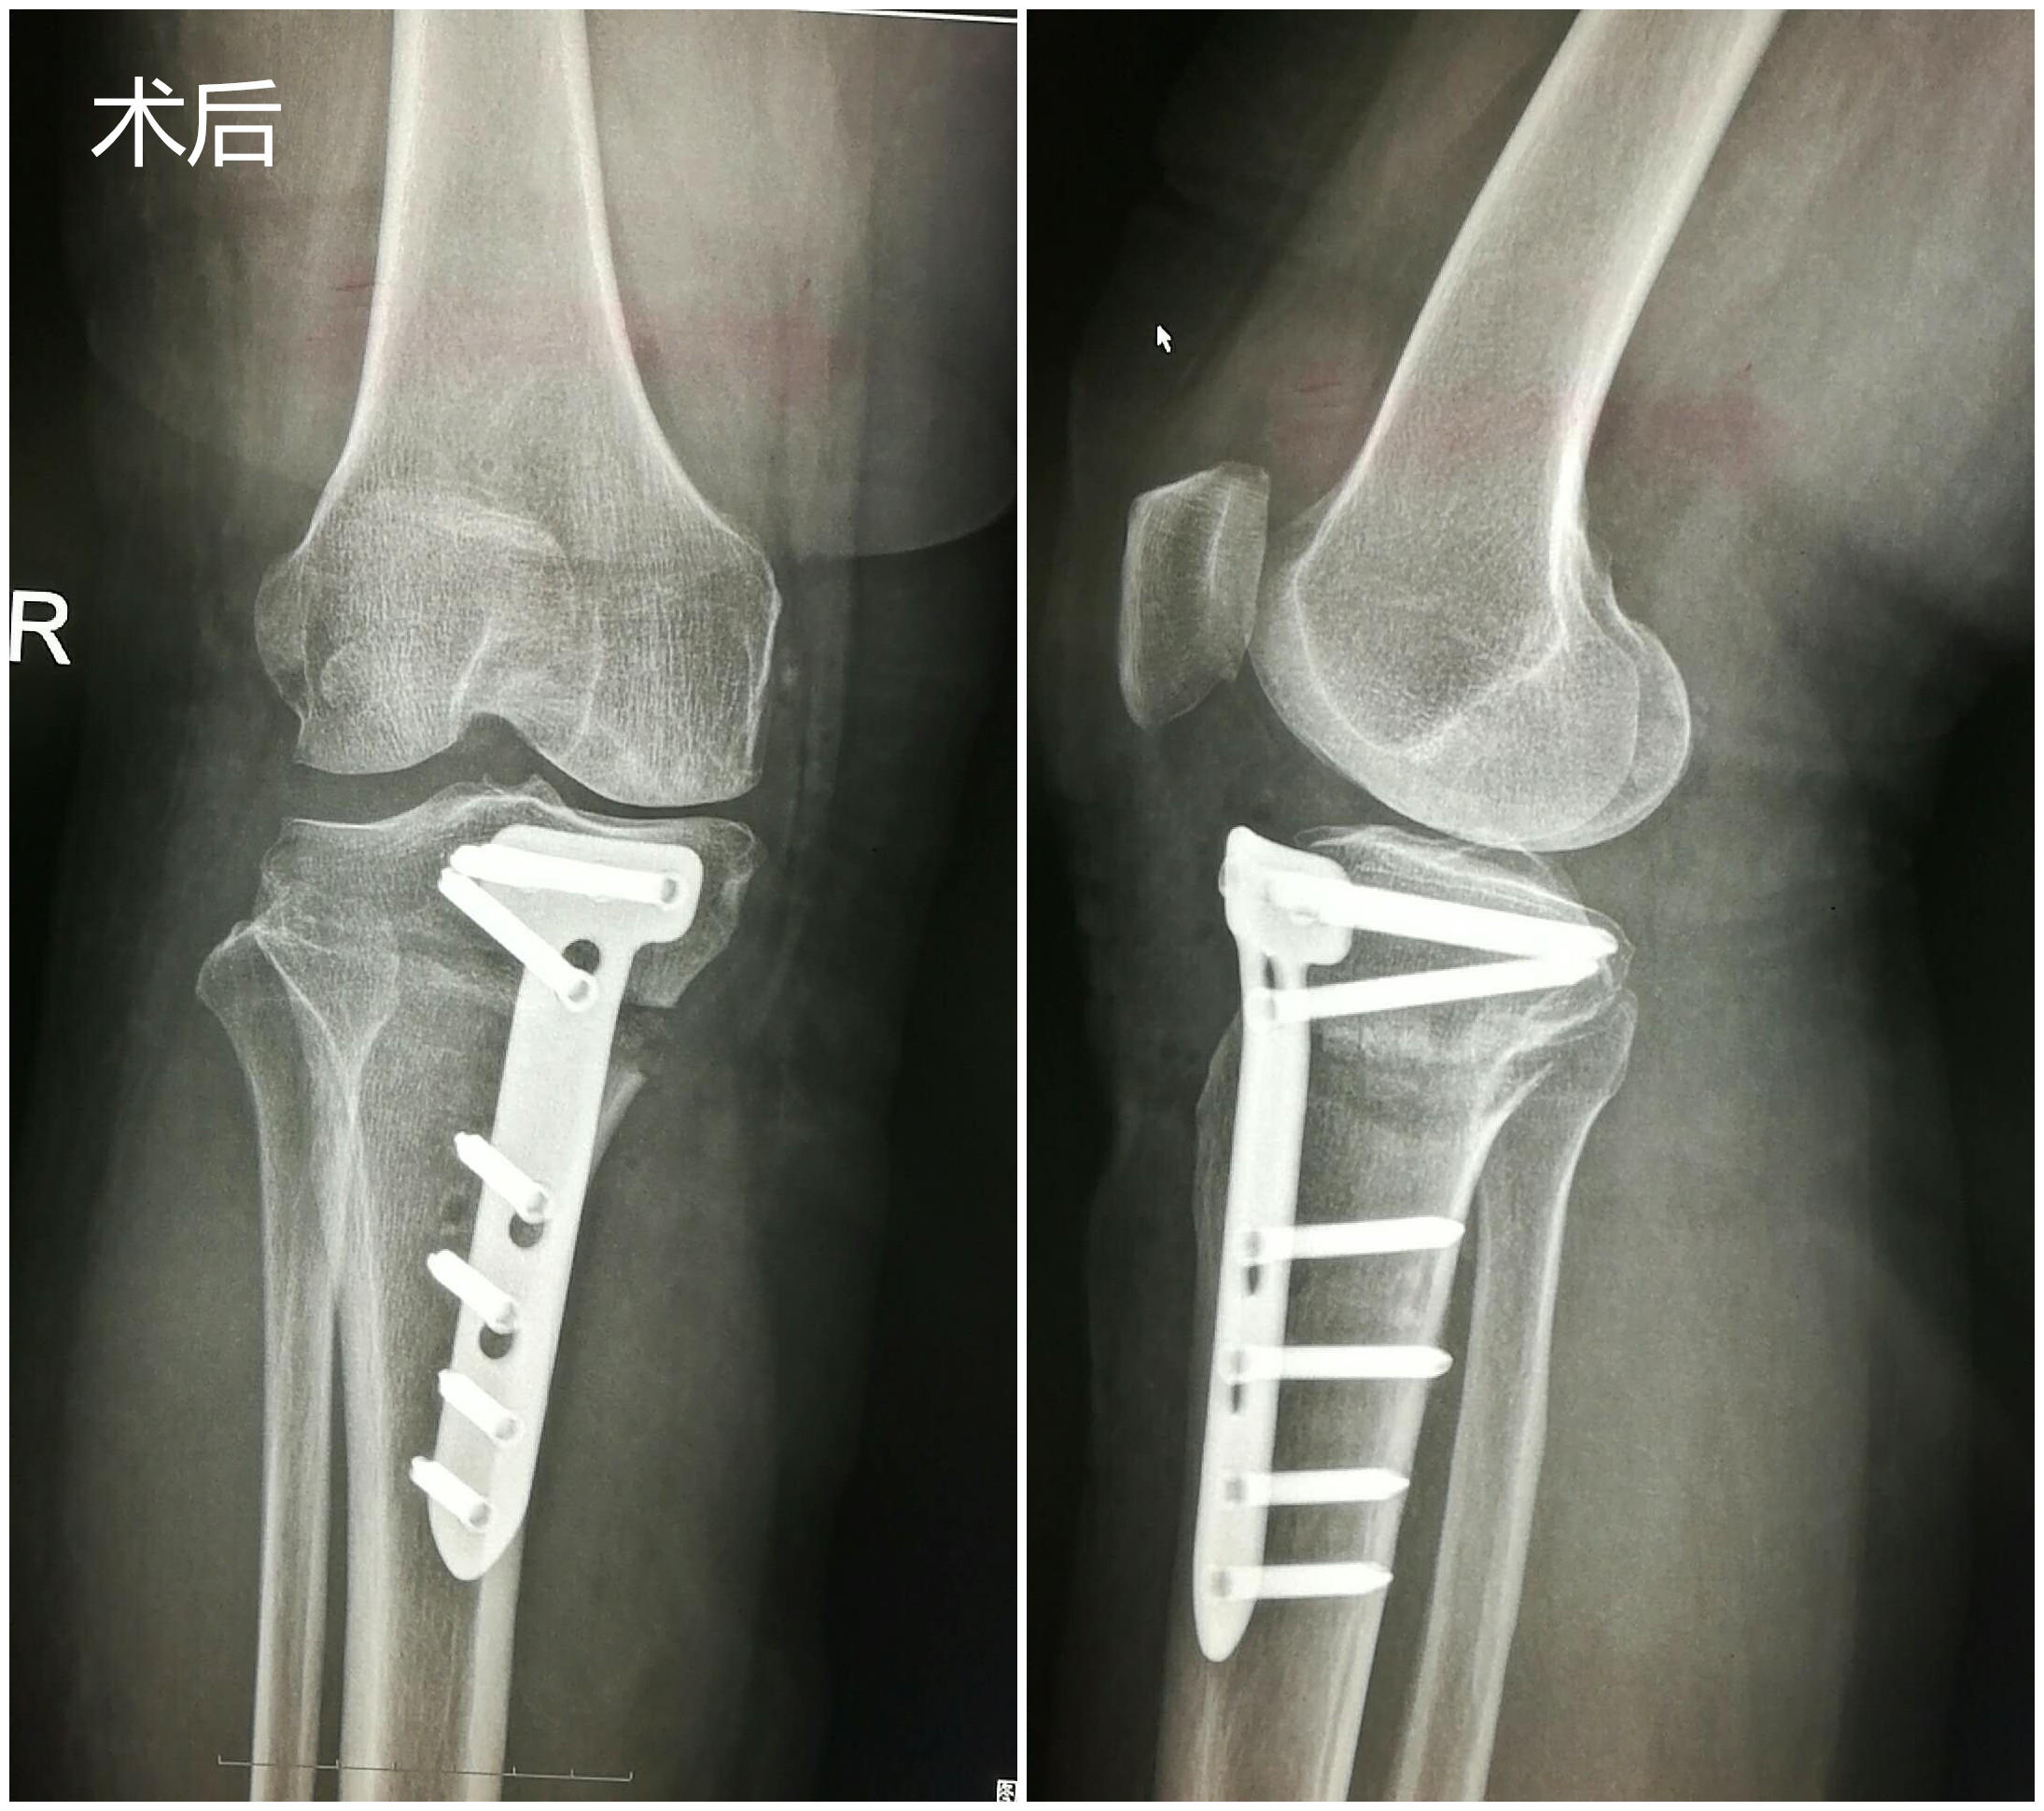

近日,我院骨一科成功完成首例右侧胫骨高位截骨术、植骨术,目前,患者病情平稳。

患者董女士,61岁,于2月前无明显诱因出现右膝关节疼痛,受凉劳累后疼痛加重,在济阳某医院行玻璃酸钠关节腔注射3次,未见明显效果,且疼痛逐渐加重。2周前,董女士自感右膝部疼痛再次加重,导致无法正常站立行走,为求进一步治疗,遂来县医院就诊,行膝关节MRI检查并收入院进一步治疗。 入院后,骨一科董孟政主任医师、张甲铠主治医师第一时间详细了解了患者病史,立即组织科室技术骨干进行病历讨论,根据患者:1.年龄较轻,只有61岁;2.仅表现为膝关节内侧疼痛,结合磁共振检查结果,考虑为单间室病变即仅膝关节内侧关节退变;3.结合下肢负重位全长片分析,其下肢负重力线內移等情况决定先不给予膝关节置换,而是采用目前更先进的胫骨高位截骨术治疗。经积极术前准备,于2017-10-21在硬膜外麻醉下实施手术,手术紧张有序进行,经过约1.5个小时,顺利完成手术。术后3天病人即能扶拐杖下床行走。目前病情恢复很快,自觉膝关节疼痛明显好转,我们将进行长期随访。

膝关节骨性关节炎是中老年常见病、多发病。关节疼痛严重者不敢负重行走,严重影响生活质量。中晚期患者保守治疗效果差,不得不接受手术治疗。以前所谓的手术治疗只有人工关节置换一种手段,但人工关节有一定的寿命,维持约15年后部分年轻患者不得不再次手术翻修,二次手术难度增加,效果也差。随着骨科技术的发展,换关节已不再是唯一、也不再是最终治疗方法。对于单间室病变(表现为单纯内侧或外侧疼痛),下肢力线不正常的中期病人,胫骨高位截骨术已成为最佳选择。胫骨高位截骨术(HTO)是通过胫骨近端截骨,把力线从磨损严重的的膝关节内侧间室转移到相对正常的外侧间室,达到改善或消除关节疼痛症状,使年轻患者推迟关节置换年龄,相当一部分甚至终生不需要再行关节置换,已成为风靡世界的膝关节骨性关节炎的治疗手段。